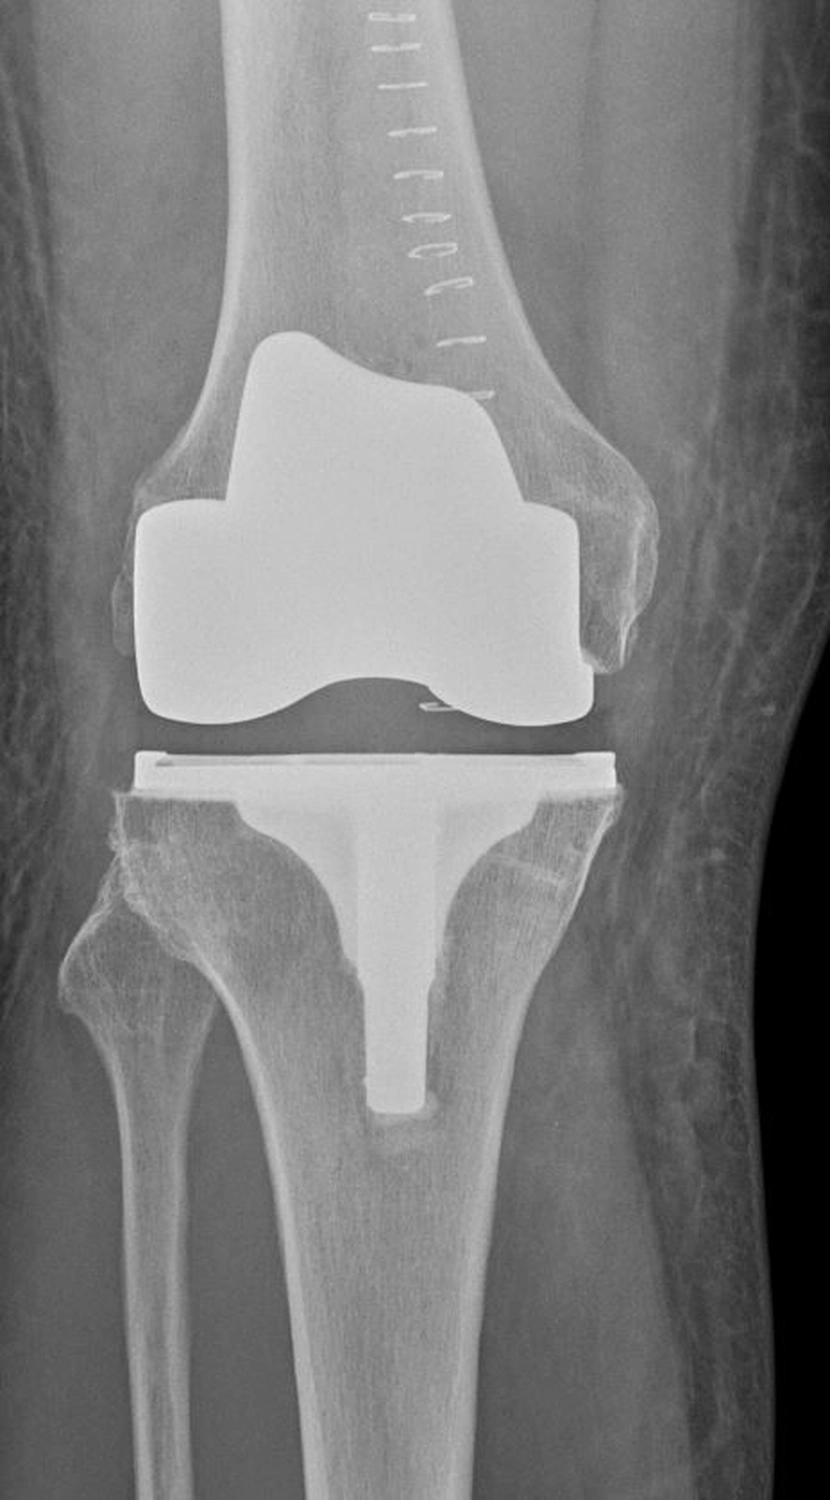

Bei der Implantation einer Knieprothese werden die zerstörten Gelenkflächen des Oberschenkel- und Schienbeinknochens millimetergenau entfernt und durch passgenaue Metallkomponenten ersetzt. Dazwischen liegt ein hochbelastbares Kunststoffinlay, dass die Gleitfläche bildet.

Je nach Schädigung und Gelenkzustand werden unterschiedliche Prothesenarten verwendet:

Die Operation dauert etwa 60 bis 90 Minuten und erfolgt unter Voll- oder Spinalanästhesie.

Moderne Knieprothesen haben eine sehr gute Haltbarkeit: In über 90 % der Fälle sind sie nach 15–20 Jahren noch voll funktionsfähig.